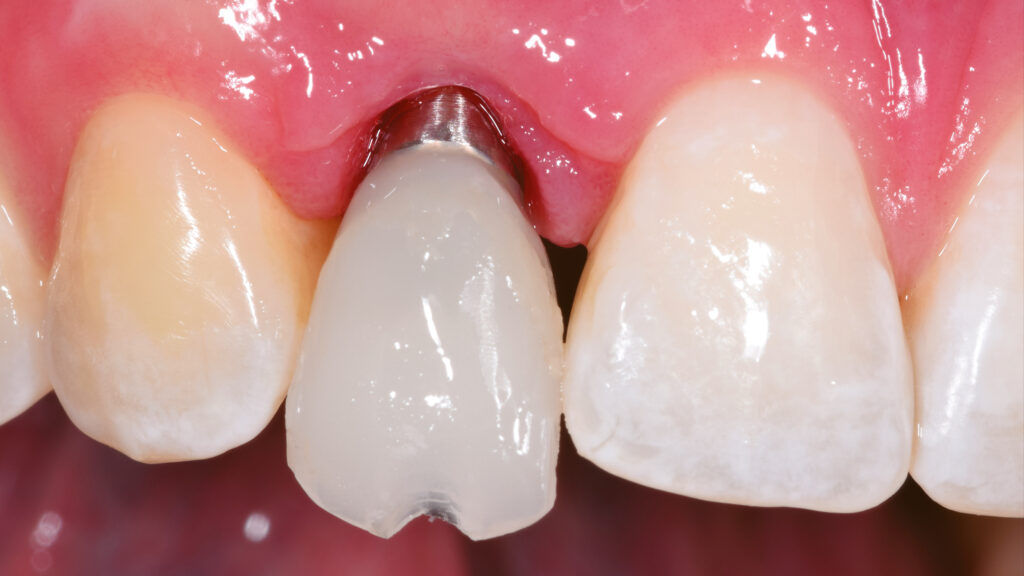

Die Gestaltung des marginalen Randes („Präparationsrand”) im bukkalen Bereich erfolgt in Absprache mit dem Zahnarzt ca. 0,2 mm subgingival (Abb. 52). Palatinal endet die Verblendkeramik supragingival, um hier die biologischen Vorteile des Zirkonoxids zu nutzen (Weichgewebekonditionierung) (Abb. 53). Vor allem im Frontzahnbereich wird das individualisierte Emergenzprofil als wichtiger Faktor für die Rekonstruktion einer zufriedenstellenden Ästhetik angesehen. Zudem werden im Frontzahnbereich mit Zirkonoxid biologisch und ästhetisch bessere Ergebnisse erzielt als mit Titan, das bei dünnem Gingiva-Biotyp durchscheinen kann (Abb. 54 und 55).

Die individuelle Formgebung der ASC-Implantatkronen ermöglicht einen reizfreien Schleimhautkontakt mit Titanadapter und konischer Innenverbindung zum Implantat (Abb. 56 und 57). Die keramische Verblendung des Zirkonoxid-Abutments erfolgt analog und ebenso detailgetreu wie beim keramischen Veneer und mit der gleichen Verblendkeramik (Lumex AC). Nach der Verblendung wird die Implantatkrone auf dem Meistermodell verschraubt und eine letzte Kontrolle der Kontaktflächen (Abb. 58 und 59), der Artikulation, der seitlichen Bewegungen und der Eckzahnführung durchgeführt. Abbildung 60 zeigt den nahtlosen Übergang der Implantatkrone zur natürlichen Gingiva. Eine Überkonturierung könnte zu einer apikalen Verschiebung führen. Eine polar_eyes-Aufnahme macht das Innere der Krone und die Details besser sichtbar (Abb. 61).

Eingliederung der Implantatkrone

Nach einigen Monaten war das periimplantäre Weichgewebe endgültig stabilisiert. Es zeigte sich noch eine leichte Narbenbildung am Gingivazenit. Nach vorsichtigem Ausdrehen der provisorischen TempShell-Krone offenbart sich eine gut ausgebildete Weichgewebsarchitektur. Die Gewebedicke an der Implantationsstelle ist vergleichbar mit der Situation am zu kopierenden linken lateralen Schneidezahn (Abb. 64). Die Zirkonoxidkrone mit Titanadapter wird definitiv mit dem Implantat verschraubt. Durch die detaillierte digitale Vorbereitung sind oft nur kleine Korrekturen notwendig. Meist können die Restaurationen ohne Einprobe eingegliedert werden. Die biokompatiblen Anteile der Implantatkrone (Titanadapter) und die subgingivalen Anteile der Implantatkrone gewährleisten eine optimale Anlagerung der Gingiva (Abb. 65). Der spaltfreie Sitz der Versorgung auf dem Implantat wird röntgenologisch kontrolliert.